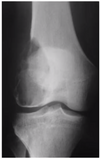

# Princípios básicos de tumores ósseos - Com base na imagem, classifique de acordo com Enneking:

- **B1 → latente** (*presença de esclerose*)